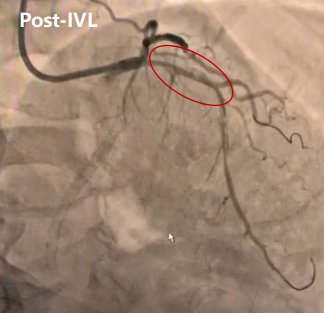

使用2.5×12mm IVL由远及近进行8个周期的预处理后植入支架,支架贴壁不良。

再次冲击波治疗:针对支架中段膨胀不良,启用3.0×12mmIVL行支架内治疗(5周期)。最终造影显示残余狭窄<10%,TIMI 3级血流。